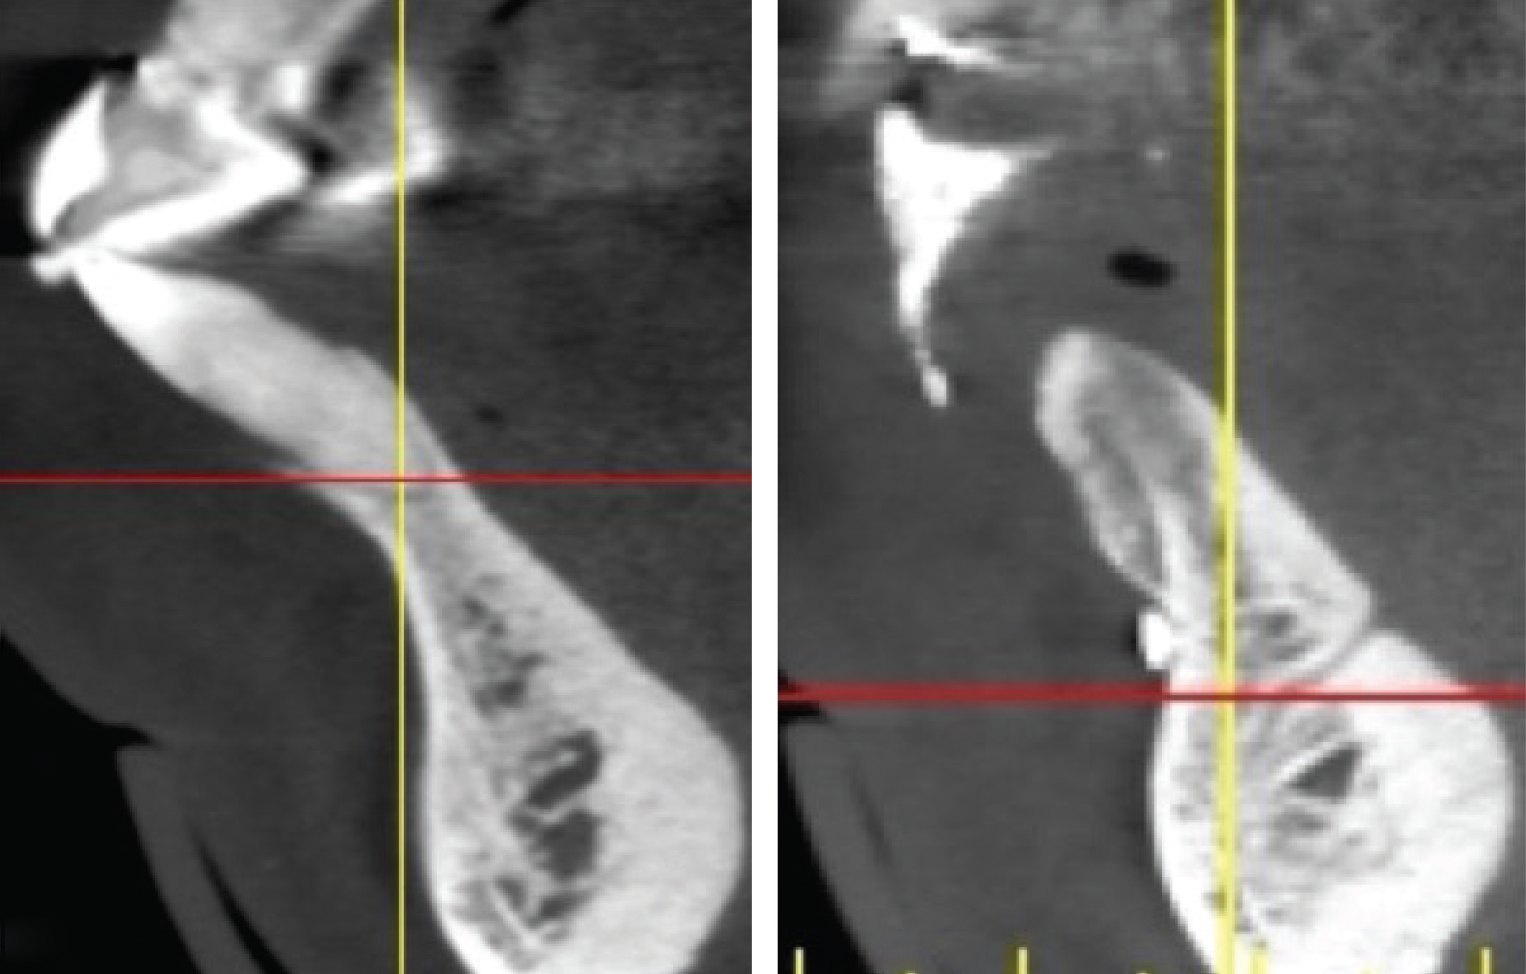

The shape and amount of bone present apical to the extraction socket is the apical topography and is important in treatment planning for both immediate and delayed implant placement. For immediate implant placement, the apical topography is significant, as 3 mm to 4 mm of native bone needs to be engaged for primary stability of the implant.1,2 If planning a 2-stage approach with site preservation and delayed implant placement, analysis of the apical topography is also essential. If a tooth with an apical concavity is extracted and a graft is placed only inside the socket, there may not be adequate bone following healing to place the implant in the proper position without additional surgical procedures3 (Figure 2). Teeth that do not have enough apical bone to provide the housing necessary for immediate implant placement or delayed implant placement with grafting inside the socket alone are defined as having inadequate apical topography. This inadequacy can be the result of periapical pathologies or the anatomy of the alveolus.

Imagery depicting examples of single-rooted sockets showing periodontium status, socket conditions, and CBCT imaging is presented in Figure 2 through Figure 5.

Grade I sockets are the most ideal. Following tooth extraction, a socket that has an intact buccal plate, adequate interproximal bone, and satisfactory apical topography will fall into this category. In this classification, an intact buccal plate is defined as having no fissures or dehiscences and less than 25% loss of height (Figure 4, left; Figure 5, left). This percentage of buccal plate loss was selected as the cutoff based on the average root length of single-rooted teeth, which is 14.2 mm,25 and the amount of buccal plate that can be reliably regenerated during immediate implant placement. Adequate apical topography is defined as enough bone present apical to the extraction site to allow for engagement of 3 mm to 4 mm of a properly positioned immediate dental implant (Figure 2).1,2 Adequate interproximal bone is defined as no or mild (up to 2 mm) periodontal bone loss on the adjacent teeth as to allow for support of the interproximal soft tissue and to enable placement of the platform of an immediate implant in the proper apical-coronal position relative to the adjacent teeth while still being bordered by bony walls on the mesial and distal aspects26 (Figure 3, left).

Grade III sockets are the most deficient and include any socket with inadequate apical topography, insufficient interproximal bone, or more than 50% loss of buccal plate. Inadequate apical topography is defined as not enough bone present apical to the extraction site to allow for implant placement and may be the result of bone loss caused by periapical lesions or concavities due to existing anatomy of the alveolus (Figure 4, right; Figure 5, right). Insufficient interproximal bone is defined as moderate-to-severe periodontal bone loss—greater than 2 mm on one or both of the adjacent teeth.